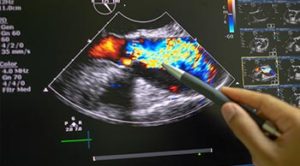

Echocardiogram